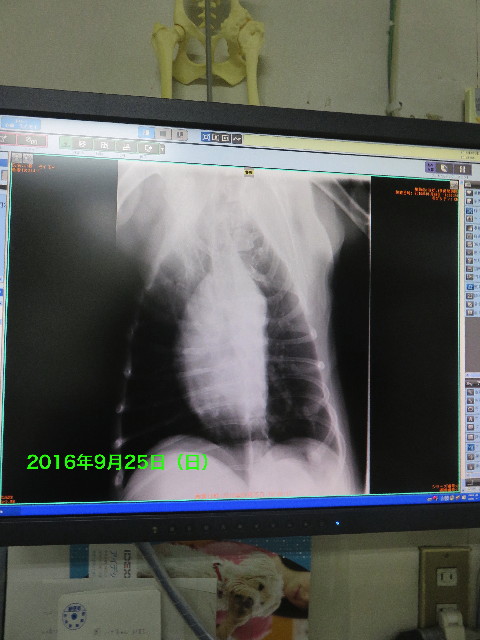

なので、続いてはおなかのレントゲン。

幸いざっと見た感じではおなかにあやしい影は無いので、とりあえず癌の可能性は低そうです。

これは2年前もこんな感じなので大丈夫そうです。

(2年前より湾曲がキツクなりましたが。)